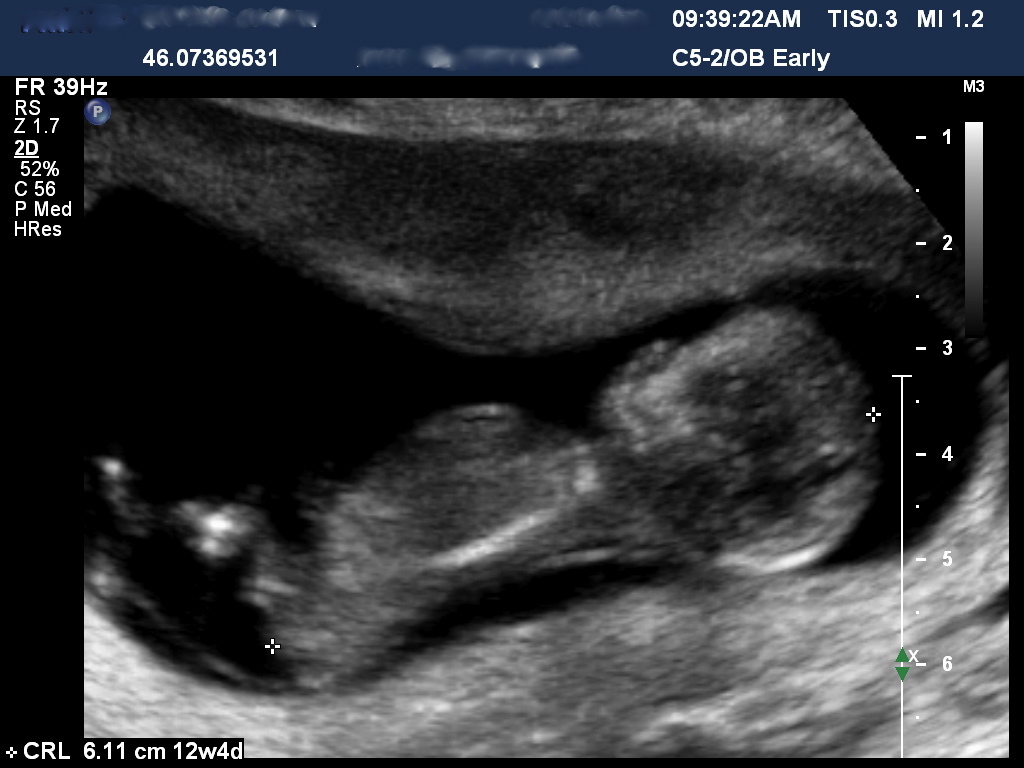

Hi All trying to pick the gender but need help please??? Boy or girl 12.5 week u/s Attachment 6766Attachment 6767

I'd got with boy. The potty shot looks boyish and the angle of the nub is upwards and not flat.

Does anyone know much about the skull theory, I've only just seen it on other posts. does it look like a boy skull to anyone :)

Yes i think the skull is boyish too, see how the forehead is kind of flat looking, where girly skulls are really rounded.

Yes, boy skull and boy nub!